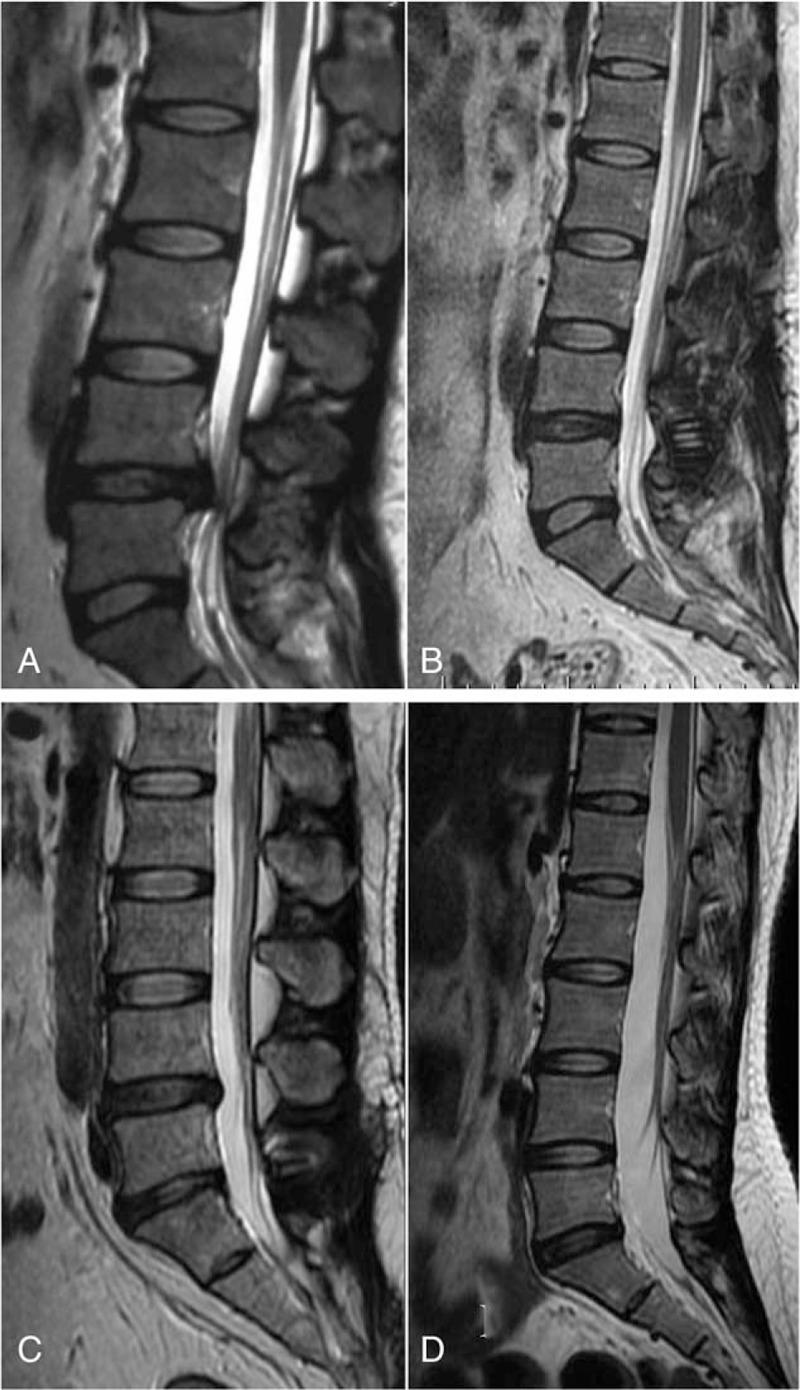

Adjacent segmental degeneration (ASD) is a major issue after pedicular fixation. This study examined the degeneration of the adjacent levels due to the insertion of the Wallis interspinous stabilization system compared with discectomy, using magnetic resonance imaging (MRI).Thirty-eight patients diagnosed with lumbar degeneration disorders at L4-L5 were reviewed: 19 patients underwent discectomy and Wallis system implantation (group A), and 19 patients underwent discectomy (group B). The Visual Analog Scale (VAS) and Oswestry Disability Index (ODI) were assessed preoperatively and postoperatively. ASD was evaluated by MRI.There was no difference in the preoperative ODI scores between the 2 groups (non-normal distribution, median, 50 (40, 50) vs 50 (50, 50), P = .331), but the postoperative ODI scores were different (non-normal distribution, median, 0 (0, 32) vs 20 (20, 30), P < .005). Similar results were observed for VAS. In group A, ASD occurred in 4 patients (21.1%) in the disc and 8 (42.1%) in the facet joint at L3/4, and in 4 (21.1%) in the disc and 5 (26.3%) in the facet joint at L5/S1. In Group B, ASD occurred in 3 patients (15.8%) in the disc at L3/4, and in 4 (21.1%) in the disc at L5/S1. In general, there was no difference between the 2 groups (P > .05), except at L3/4 (P = .015).ASD of the facet joint in the cranial segment occurred after Wallis system implantation, suggesting that the Wallis system cannot prevent ASD of the facet joint, but could have some other benefits for the discs.